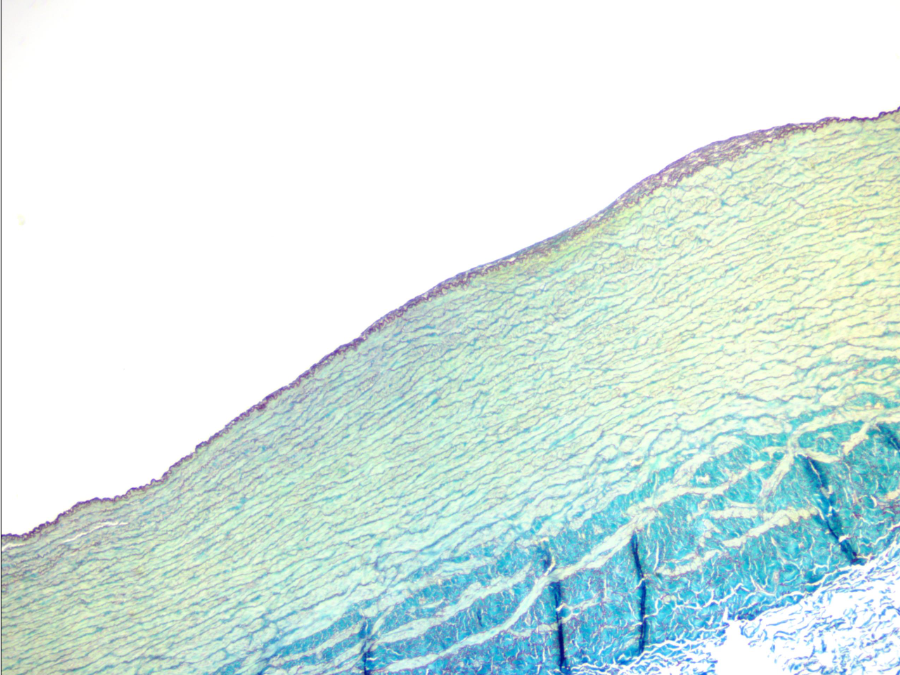

Arteria coronaria (muscular)

Túnica media con fibras musculares lisas

La túnica adventicia en arterias musculares es la más grande